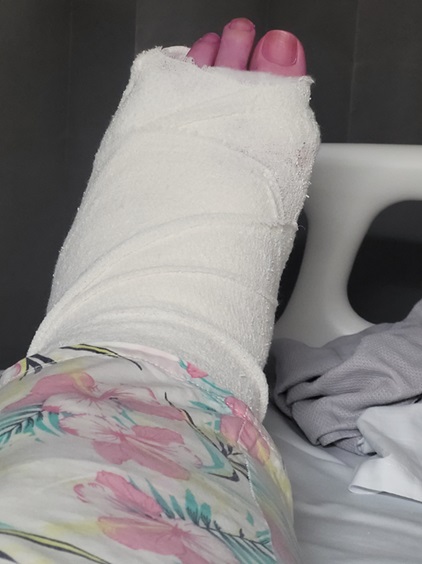

This issue will not apply to all surgeries either. It depends how long your post-op period is AND the degree of immobility required. For example, I’ve had both ankles fused. Same post-op period in both cases. However, with the left ankle I could drive four weeks earlier than with the right ankle and that four weeks, plus an additional, unrelated, hospitalisation, were enough to make what was, in my case, a major difference.

When I had the left ankle done in 2023, by the time I was in a moonboot and on crutches I could drive to the gym and do the weighted back exercises I needed to do to maintain my posterior chain strength. With the right ankle, obviously I couldn’t drive for an additional month. Then, two weeks after I could drive, I was back in hospital for a nasal/sinus infection. Essentially immobile again.